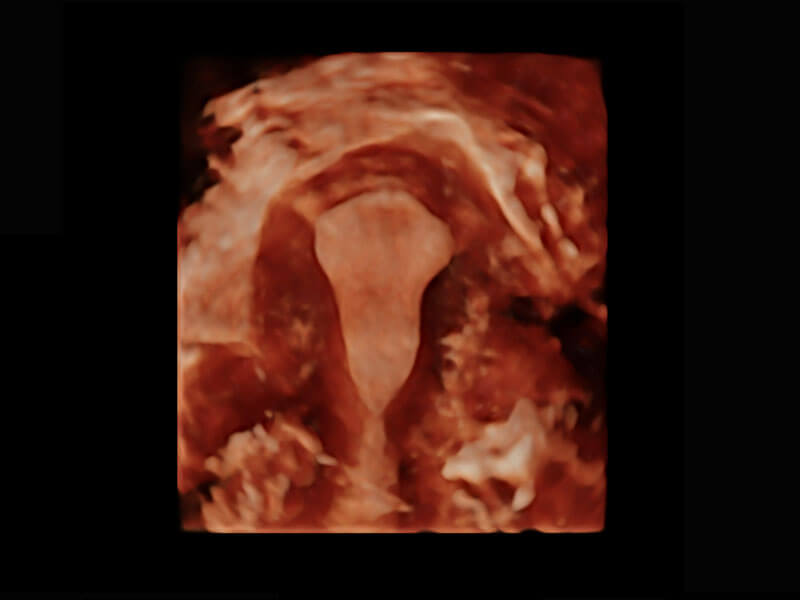

P60搭载一系列胎儿心脏成像技术,实现精细的胎儿心脏评估。

四腔切面

四腔心血流

右室双出口

胎心容积成像